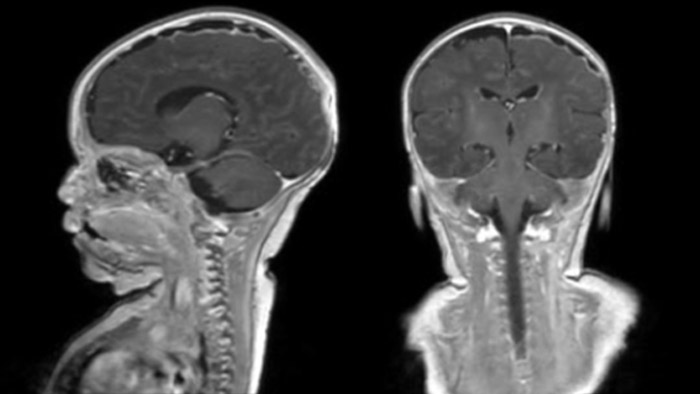

Dural sinus malformation (DSM) Initial examination

After three times of coiling and acryl based embolization